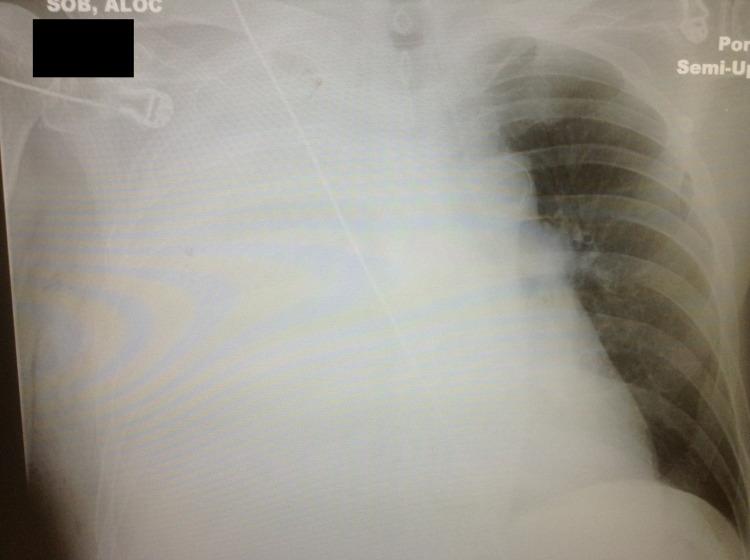

An empyema necessitans is a rare complication of a collection of purulent material in the pleural space that spreads outside of the pleural cavity and involves the soft tissues of the chest wall. Due to compression forces created by the size of the collection of empyema in the chest cavity, patients are usually symptomatic and present with severe dyspnea. Chest X-ray or ultrasound of the chest cavity are the ideal screening tools to visualize the empyema and followed by computerized tomography scan of the chest to confirm the presence and extent of the pathology. In rare occasions, the empyema can rupture spontaneously, which may lead to critical situation requiring emergent intervention. We report the case of a 72-year-old male who presented to the emergency department with severe dyspnea and was diagnosed with empyema necesitans. During the initial management of the case, the empyema necessitans ruptured spontaneously and required emergent interventions to stabilize the patient.

脓胸穿破胸壁是胸腔内脓性物质积聚的一种罕见并发症,该脓性物质会扩散至胸膜腔外并累及胸壁软组织。由于胸腔内脓胸积聚的大小产生的压迫力,患者通常会出现症状并表现为严重呼吸困难。胸部X线或胸腔超声是可视化脓胸的理想筛查工具,随后进行胸部计算机断层扫描以确认病变的存在和范围。在极少数情况下,脓胸可自发破裂,这可能导致需要紧急干预的危急情况。我们报告一例72岁男性患者,因严重呼吸困难就诊于急诊科,被诊断为脓胸穿破胸壁。在该病例的初始治疗过程中,脓胸穿破胸壁自发破裂,需要紧急干预以稳定患者病情。